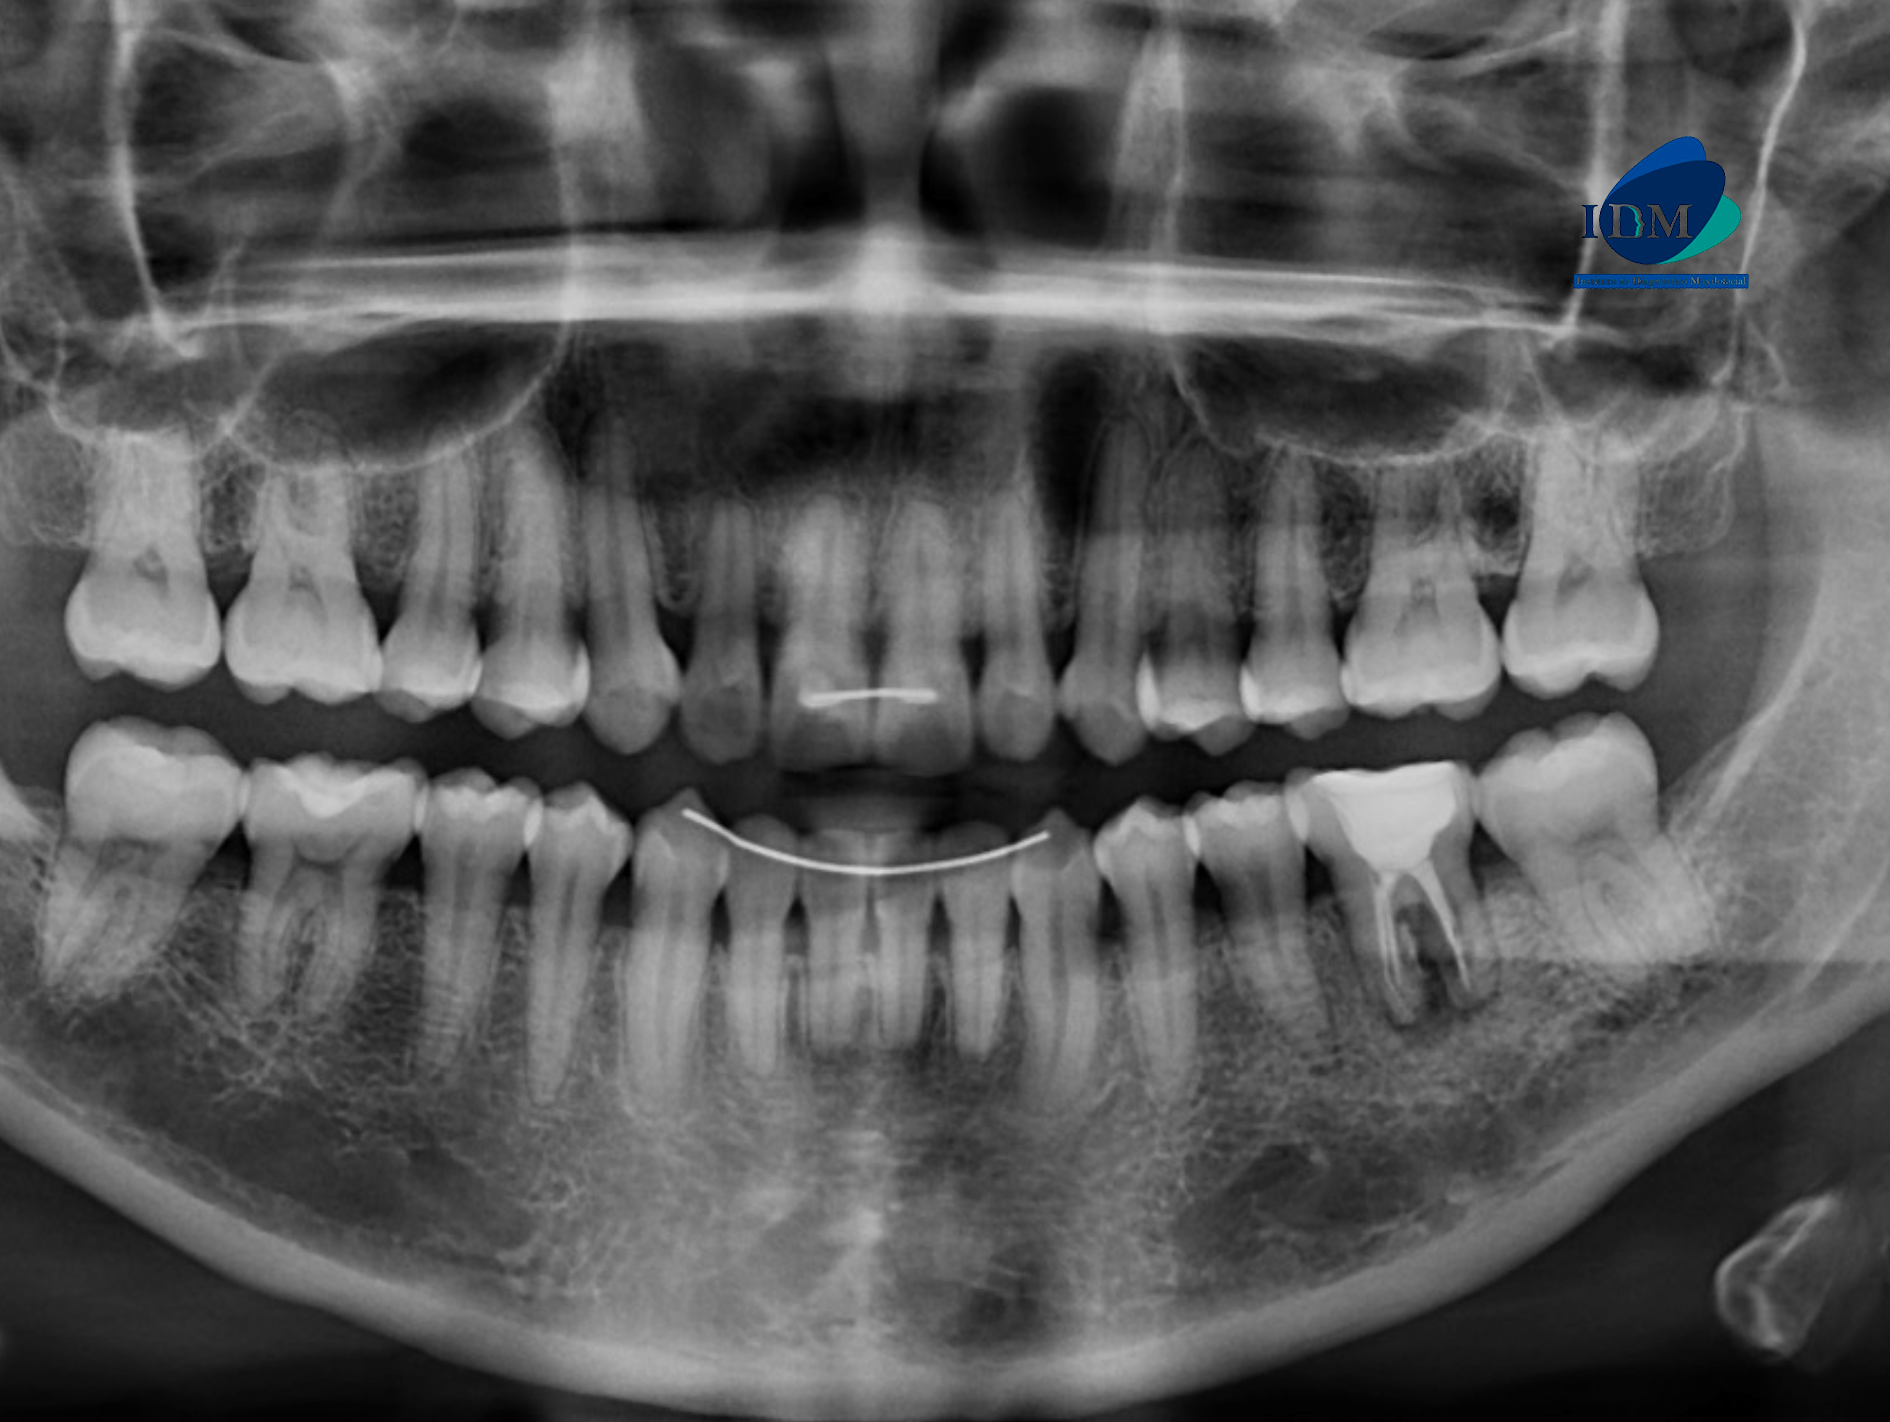

Radiografia Panorámica

A la evaluación de la radiografía panorámica se observa aplanamiento de contornos condilares, neumatización de ambos senos maxilares, presencia de dispositivos de ferulización anterosuperior y anteroinferior, ausencia de terceras molares y múltiples restauraciones, también observamos la pieza 36 con material restaurador coronario, sellado cameral y obturación de conductos con un proceso osteolítico interradicular y una imagen radiolucida en raíz distal.